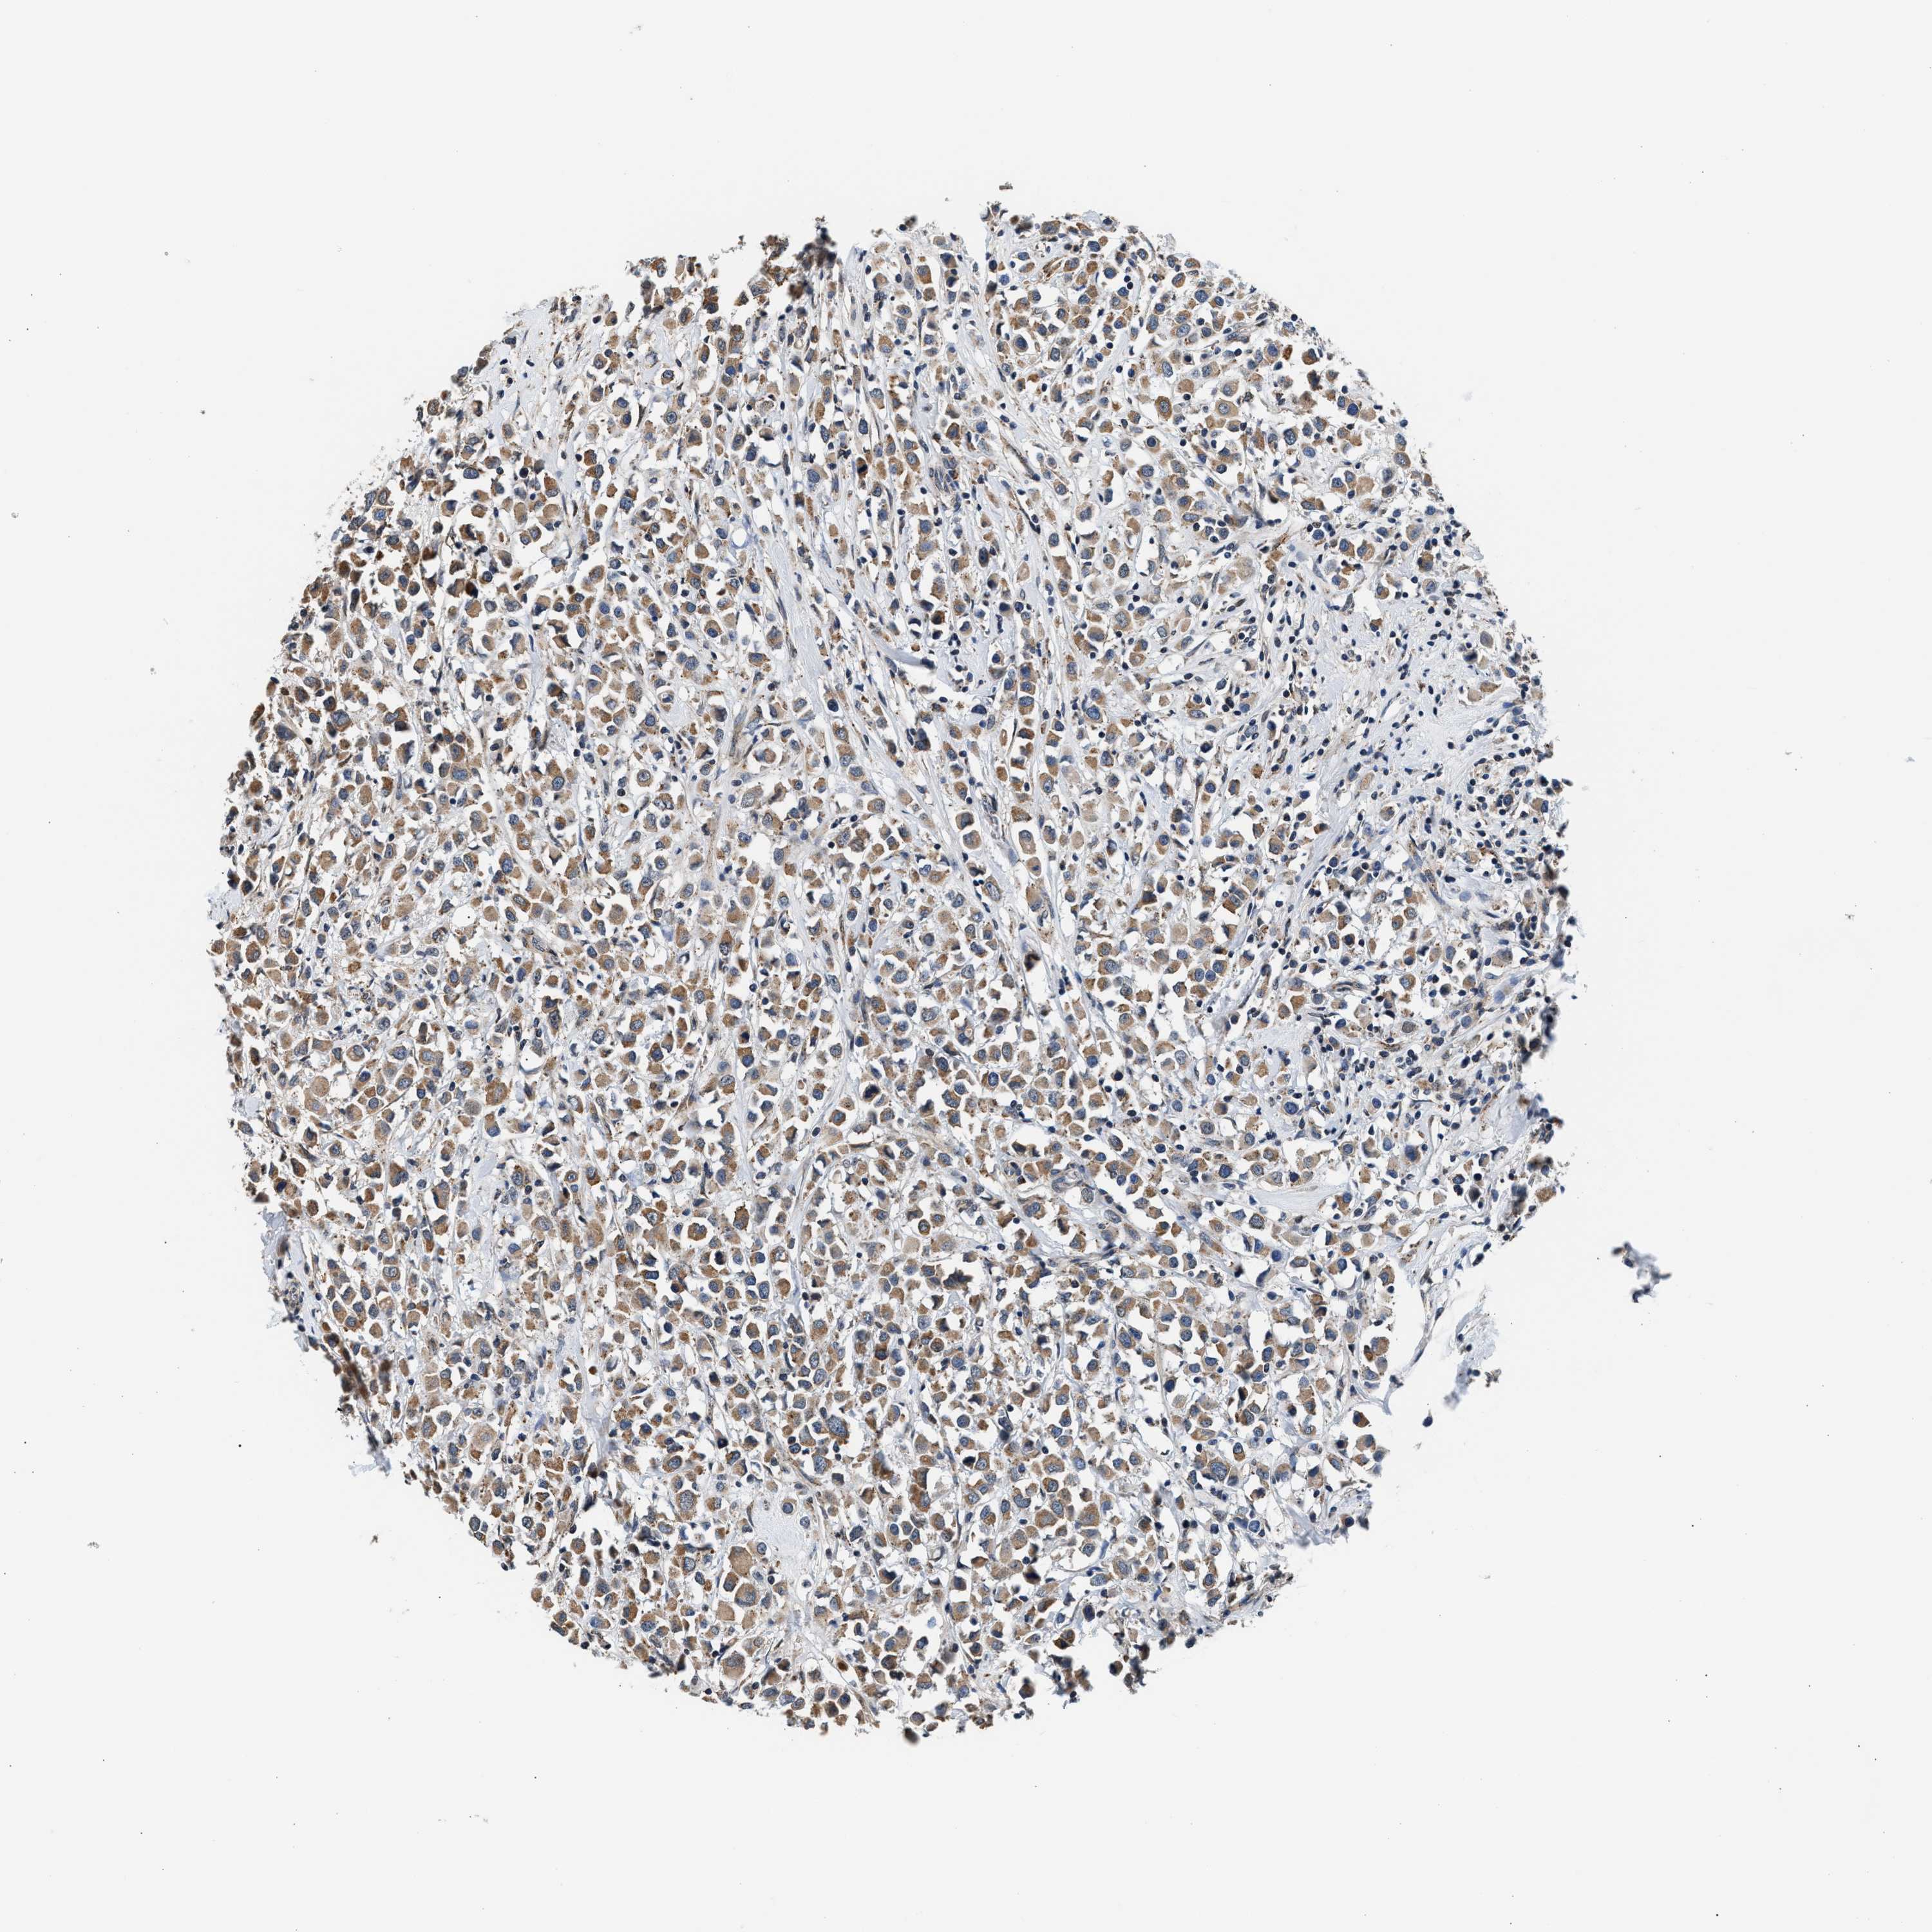

CANCER BREAST CANCER Show tissue menu

BRCA TCGA BRCA VALIDATION PROTEIN EXPRESSION